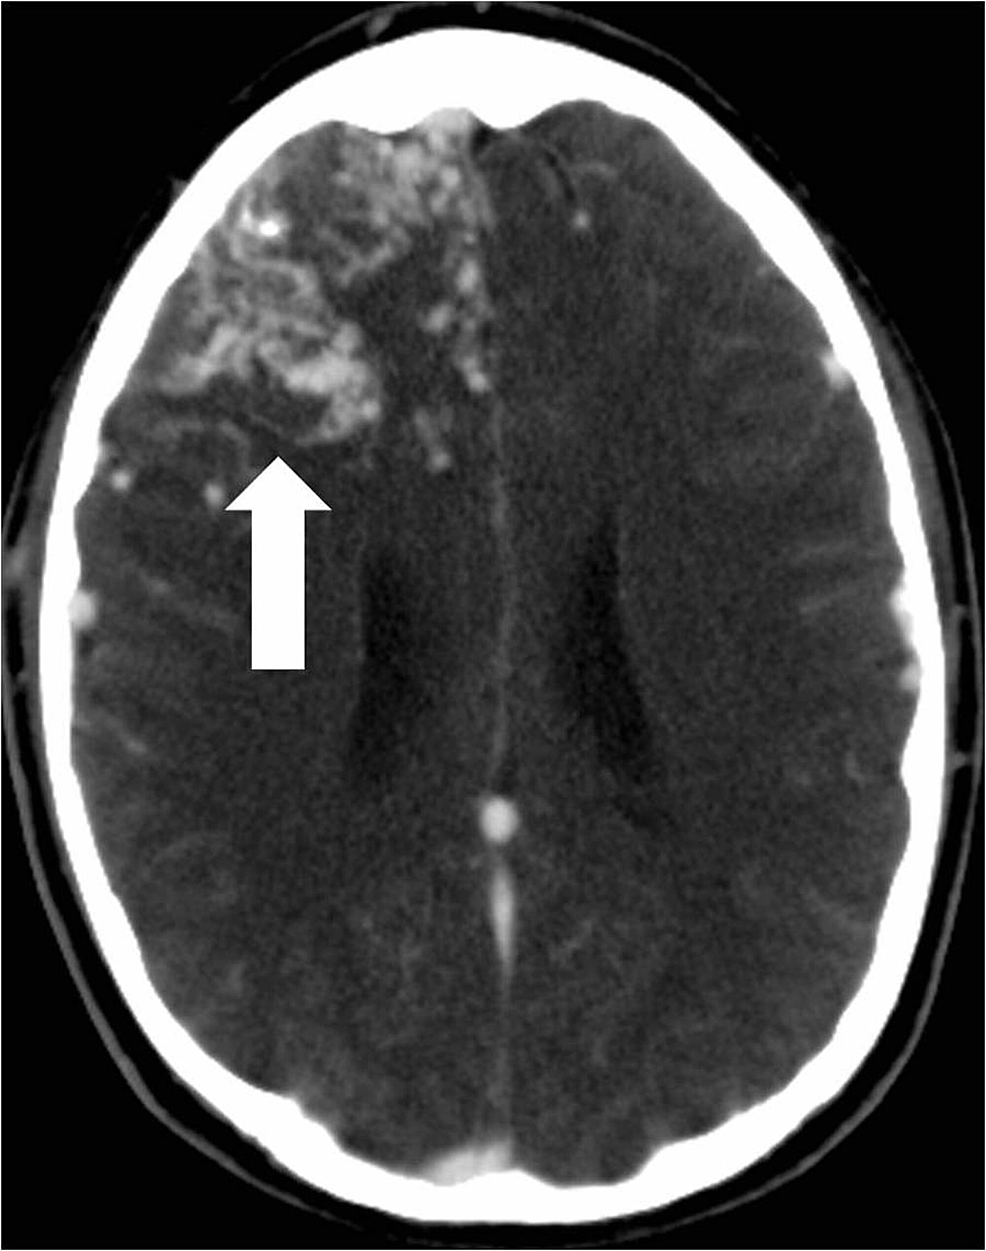

Each pedicle was treated with a combination of polyvinyl alcohol (PVA) particles (ranging in size from 250 to 500 microns), gelfoam torpedoes, and platinum coils of varying lengths and sizes. A post-embolization arteriogram demonstrated greater than 80% reduction in the overall angiographic volume of the arteriovenous malformation nidus (Figure 4).

The right middle cerebral artery feeding pedicles were not embolized due to their superficial location and ability to secure these pedicles upon initial surgical approach. The following day, the patient underwent a right frontoparietal craniotomy to resect the AVM. A subsequent postoperative head CT revealed no complications (Figure 5).